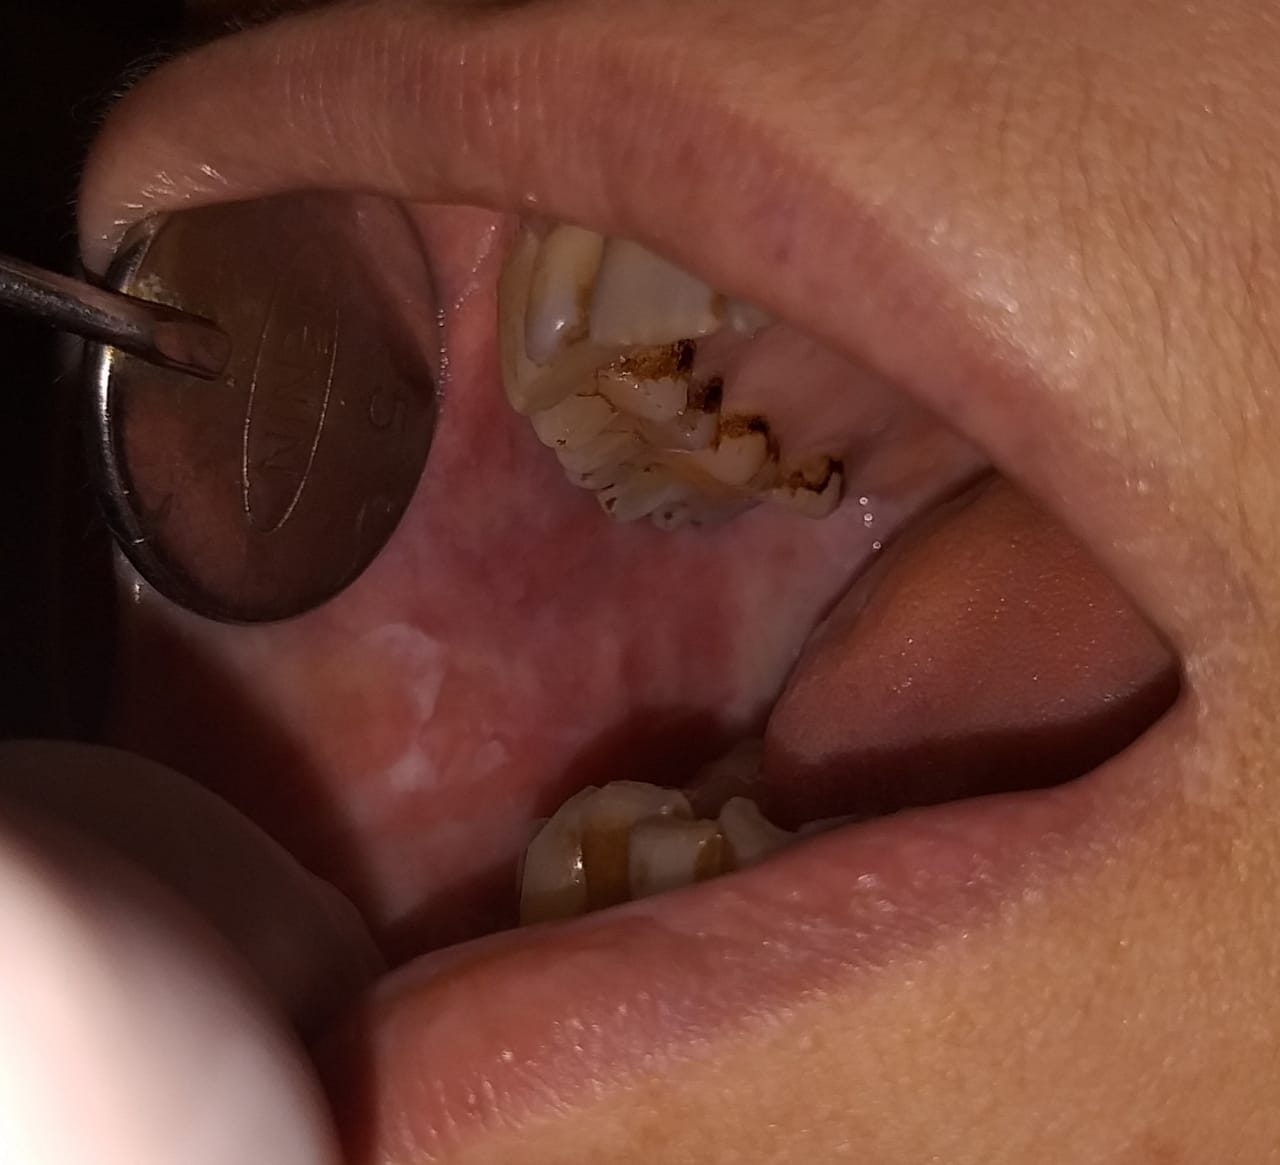

Chronic periodontitis, considered as the 6th complication of diabetes is detected early by dental check up. Other oral manifestations of diabetes can also be detected early and treated with utmost care.